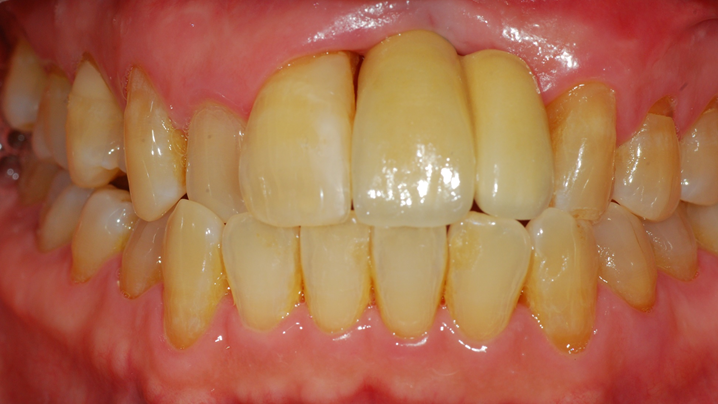

Clinical case: Peri-implantitis treatment case using titanium or NiTi brush

- Courtesy of Dr. Dae-Hee Lee, South Korea -

Dr. Dae-Hee Lee,Maxillary Anterior,Peri-implantitis,Bone regeneration,Aesthetic zone,#21,#22,GBR,Titanium Brush Set